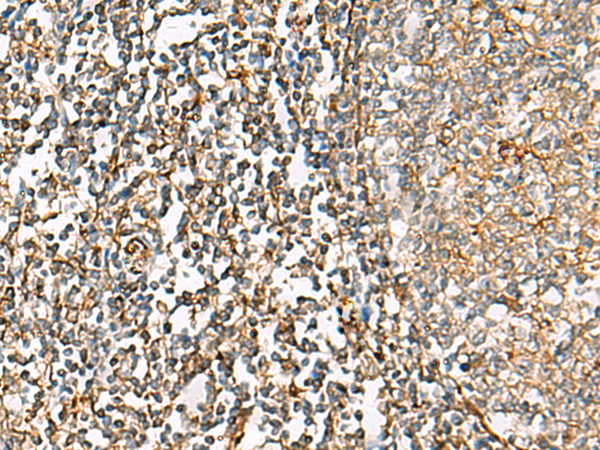

ELISA, IHC |

IHC positive control: |

Human liver cancer and Human tonsil |

IHC Recommend dilution: |

50-100 |